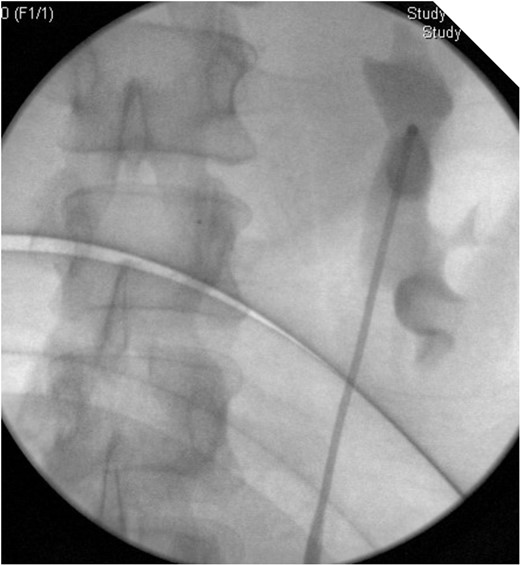

On table Pyelogram confirmed intact left collecting system and ureter.

On stent removal, we performed an on table retrograde pyelogram to confirm there is no residual leakage and also to exclude significant stricturing. A CT IVU after stent removal may also be considered as an alternative to this approach.